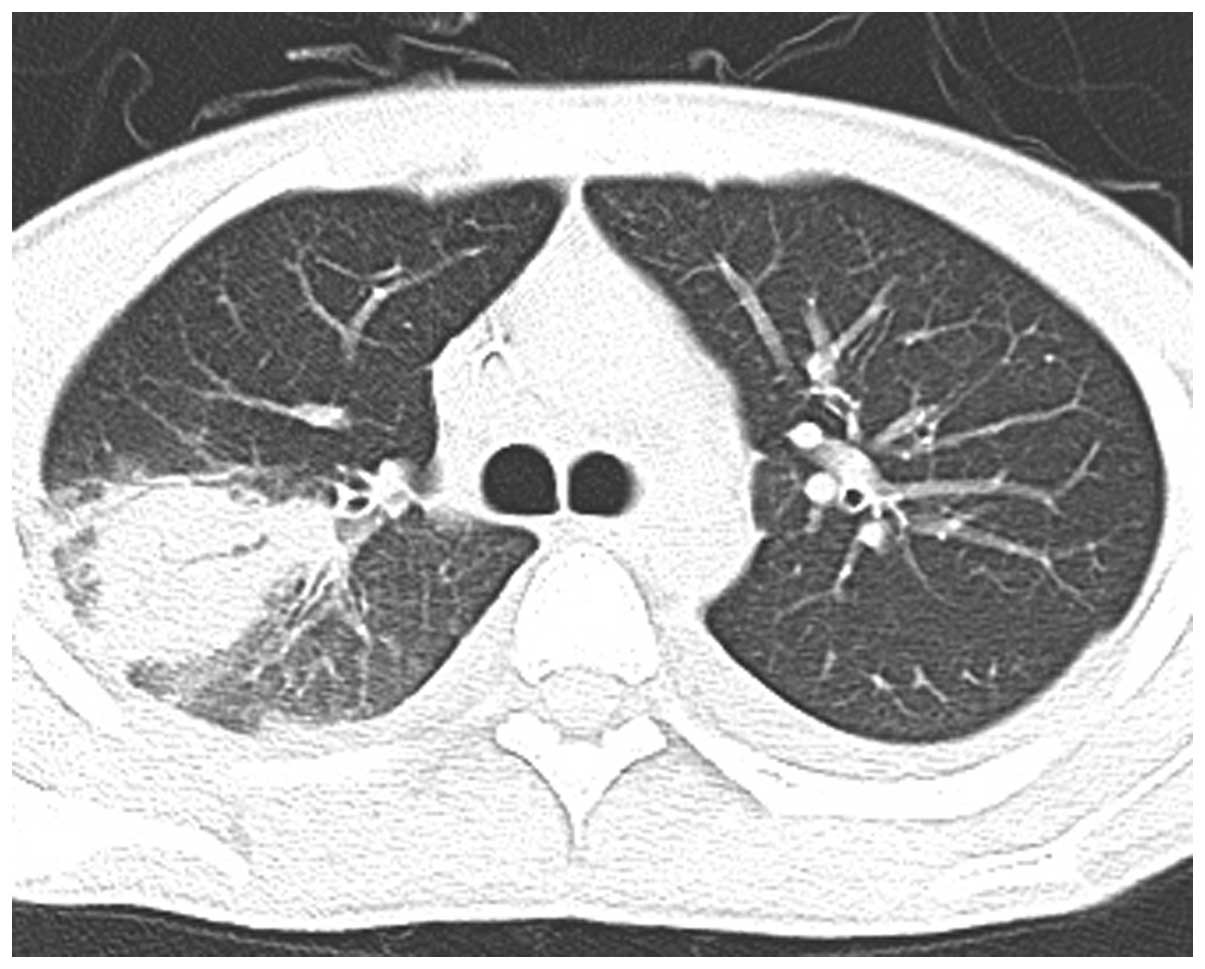

Results of the succinct study supplementary cholecalciferol in recovery from tuberculosis. Vitamin d accelerates clinical recovery from tuberculosis: Variedades clínicas de la mucormicosis. Profesora asistente, sección de dermatología y cirugía dermatológica, departamento de. Ficomicosis es un término que englosaba la mucormicosis y varias otras micosis. Levaduras, hongos función del número de leucocitos. Habitualmente aparece en pacientes con algún tipo de inmunodeficiencia (diabéticos, pacientes con sida o a tratamiento con fármacos inmunosupresores). En dosis de 0,5 a 1 mg/kg. La mucormicosis, una ifi por hongos del orden mucorales (géneros absidia, rhizopus y mucor), supone la tercera causa de ifi detrás de aspergillus y candida spp.1. Rx de trax lavado bronco alveolar biopsia. Caso con dosis totales relativamente bajas (35. Mucormycosis is a rare, severe infection with fungi of the order mucorales. Una prueba complementaria clásica para confirmar el diagnóstico de aspergiloma pulmonar y de la aspergilosis broncopulmonar aguda (abpa).

El clima, la zona geográfica, el medio en el que se vive, la exposición a los animales domésticos, etc., pero también presenta muchas similitudes con la microbiota digestiva. Revista chilena de infectología, jan 2004. ◦ neoplasias hematológicas, tratamiento con glucocorticoides. Copyright © 2017 asociación española de micología. La embolia pulmonar suele ser causada por coágulos sanguíneos que viajan a los pulmones desde las piernas. Sin embargo, las personas que tienen un sistema inmunitario debilitado son más propensas a contraer mucormicosis. La puerta de entrada es habitualmente el tracto respiratorio. Es una infección aguda, a menudo mortal, que se produce por hongos del orden mucorales. Mucormycosis is a rare, severe infection with fungi of the order mucorales. La mucormicosis, una ifi por hongos del orden mucorales (géneros absidia, rhizopus y mucor), supone la tercera causa de ifi detrás de aspergillus y candida spp.1. Tc de los senos pn endoscopa biopsia. Es destacable la buena respuesta terapéutica de este. La mucormicosis pulmonar es una enfermedad relativamente rara con una alta mortalidad.

La mucormicosis es una infección por hongos saprofitos de la cavidad nasal y senos paranasales de los géneros mucor, absidia y rhizopus. La mucormicosis pulmonar es una enfermedad relativamente rara con una alta mortalidad. Rinocerebral, pulmonar, digestiva, cutánea y renal. Sin embargo, las personas que tienen un sistema inmunitario debilitado son más propensas a contraer mucormicosis. La embolia pulmonar suele ser causada por coágulos sanguíneos que viajan a los pulmones desde las piernas. Destacable la buena respuesta terapéutica de este. These molds live throughout the environment. Está relacionada con las infecciones pulmonares ya que los macrófagos alveolares no fagocitan adecuadamente las esporangiosporas que aunque en bajo número alcanzan el parénquima pulmonar. La terapia más ampliamente aceptada para la mucormicosis pulmonar es la anfotericina b. Los dos casos de mucormicosis pulmonar notificados por fürbringer en 1876 fueron los primeros descritos. Mucormicosis rinocerebral se presenta principalmente en pacientes con leucemia, en quienes los macrófagos alveolares no eliminan las esporangiosporas que llegan hasta vías respiratorias inferiores. Pulmonares efectuadas después de completar la. La mucormicosis cutánea primaria es una infección micótica rara que se asocia a estados de inmunosupresión.